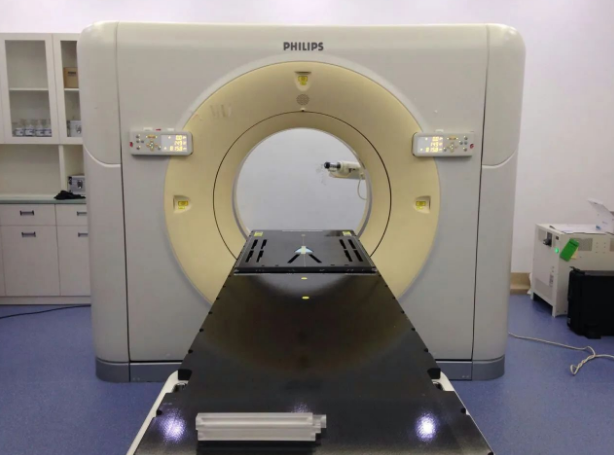

PHILIPS 16排大孔径肿瘤4D-CT模拟定位机